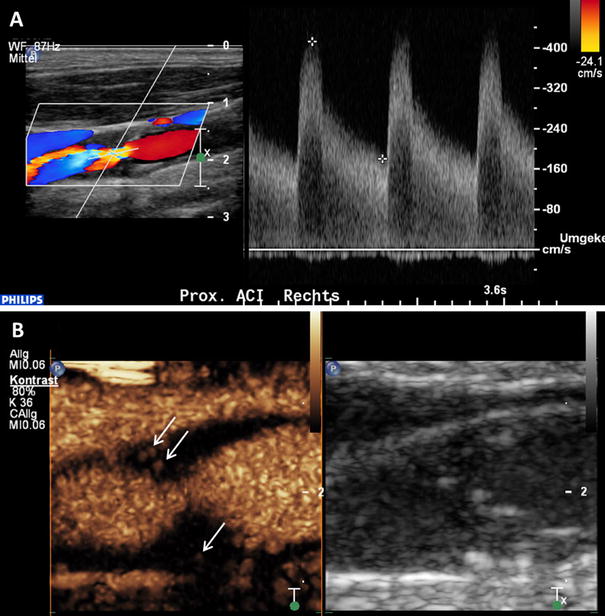

Intraplaque neovascularization within carotid stenosis on CEUS imaging. a 77-year-old patient with asymptomatic high-grade stenosis at the origin of the right internal carotid artery on Duplex ultrasound. b Extensive intraplaque neovascularization within the carotid stenosis at the near wall on CEUS imaging (arrows) and moderate neovascularization at the fare wall (arrow)

Furthermore, clinical vascular symptoms have been correlated with the presence of intraplaque neovascularization on CEUS. Retrospective studies including our own have shown pronounced intraplaque neovascularization on carotid CEUS imaging in patient with past cerebrovascular and coronary events [43, 49, 50, 51, 52]. This result supports the concept that the vascular risk assessment based on the carotid vessel wall alterations, particularly the degree of intraplaque neovascularization is not limited to the cerebrovascular bed but also generalizable to the coronary and maybe also the peripheral vascular system.